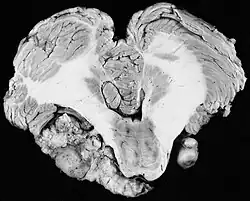

In 1777, Eduard Sandifort of Leiden, the Netherlands, wrote a postmortem first description of a vestibular schwannoma. He observed "a certain hard body adherent to the auditory nerve," and concluded this cause of deafness was beyond the reach of medication or surgery and was therefore incurable. The Schwann cells that multiply to form a VS on the vestibulocochlear nerve were identified 60 years later in 1838 by the German physiologist Theodor Schwann. In 1895, Thomas Annandale, a general surgeon at the Royal Infirmary in Edinburgh, Scotland, was the first to successfully localize and surgically remove a VS.[43] Finger dissection of VS to 'shell out' the tumor was typical. The main goal when dealing with large tumors was preservation of life.

In the early 1900s the mortality rate for VS surgery was in the range of 75 to 85%. Surgeons typically delayed invasive intervention as long as possible as a last resort. Harvey Cushing (1869–1939) is known as 'the father of neurosurgery for VS.' His basic study published in 1917 was entitled Tumors of the Nervus Acusticus and the Syndrome of the Cerebellopontine Angle. Cushing perfected the retrosigmoid surgical approach, and by doing suboccipital craniotomy and subtotal removals he was able to reduce mortality to 4% by 1931. Cushing worked at Brigham Hospital in Boston. An equally famous specialist for VS at Johns Hopkins in Baltimore was Walter E. Dandy (1886–1946), a former pupil of Cushing who advocated total tumor removals. In 1931, he reported a complete removal with preservation of the facial nerve.